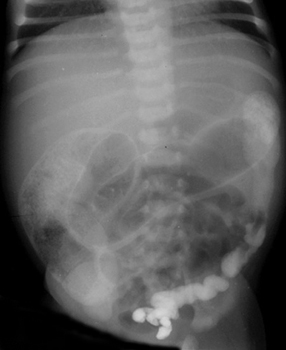

Hirschsprung Disease

Hirchsprung Disease is aganglionosis of the colon with absence of parasympathetic ganglia in mucosal and submucosal layers of colon. This is a result of the failure of normal cranial-caudal migration of ganglion cells. The most common transition site is the rectosigmoid colon. Total colonic aganglionosis is rare. The

incidence is 1 in 5,000-8,000 live births, with a male to female ratio

of 4-9 to 1. Patients may present with failure to pass meconium within

the first 24 hours of life or later with constipation and paradoxical

diarrhea (25%). The treatment is a surgical pull-through procedure. |

| The transition zone is near the splenic flexure. |